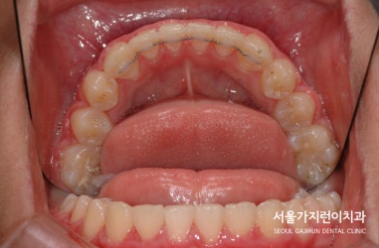

오늘은 상악의 돌출 케이스를 설명해볼텐데요. 치아의 배열 공간이 심하게 부족했던 성장기 환자의 비발치 교정이기 때문에 좀 더 까다로운 교정과정일 수밖에 없었습니다. 환자 분의 경우 상악골의 과성장과 하악골의 열성장이 종합적으로 발현된 케이스로 상악괄의 과성장을 조절하고 상악 견치 및 소구치의 맹출 공간을 확보하기 위해 상악 어금니의 후방이동이 필요했는데요. 그 과정에서 헤드기어라는 장치를 이용한 치아교정이 이루어졌습니다.

이후에는 돌출감을 해소하기 위한 미니스크류를 활용한 치아교정이 이루어졌는데요. (미니스크류는 잇몸에 박혀있는 작은 나사와 같은 장치를 말합니다. ) 미니스크류는 간단한 국소마취로도 식립이 가능하고 잇몸뼈에 직접 식립하기 때문에 강력한 고정힘으로 정밀하게 치아이동이 가능한데요. 치료를 하지 않았다면 치아의 배열이 심하게 비뚤어지고 상악 전치가 뻐드러졌을 것을 1차 성장교정(헤드기어)를 통해 만족할 수 있는 경과를 만들어냈습니다.